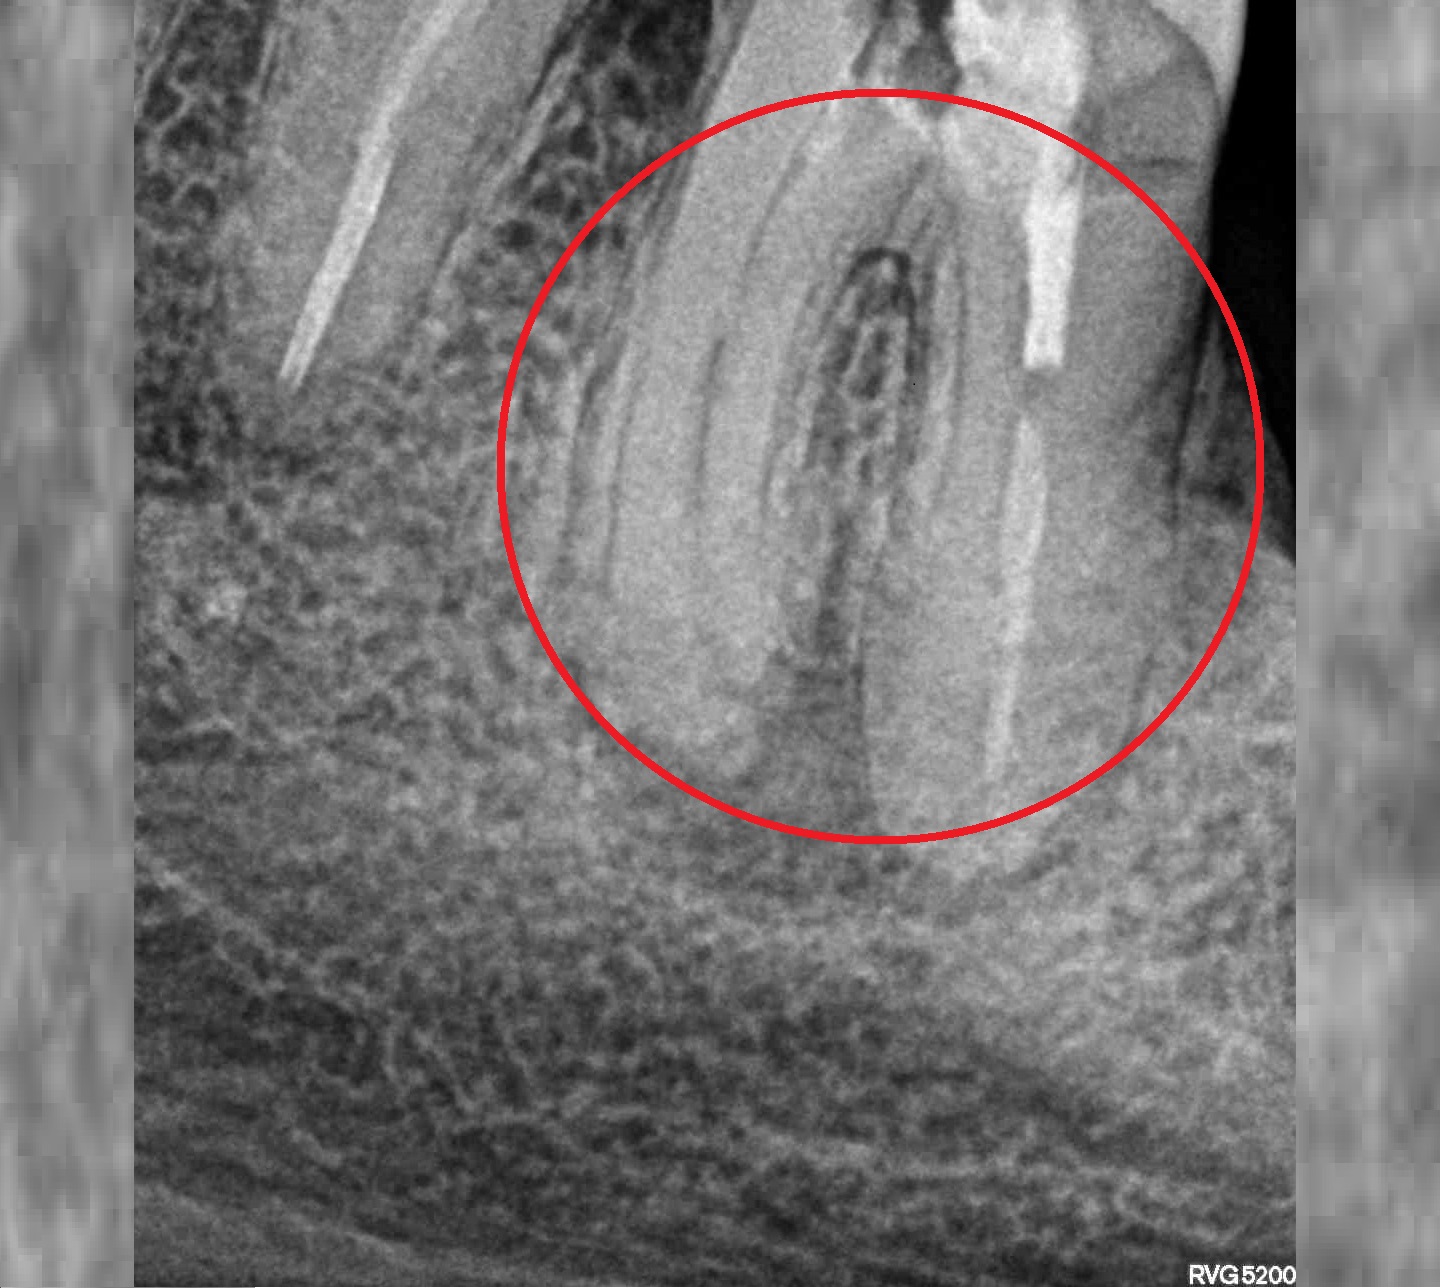

- Лечение пульпита

Проблема

Пациент обратился в клинику с жалобами на боли ноющего характера, усиливающиеся при надкусывании на зуб, реакция на холодное и горячее, так же на наличие глубокой кариозной полости, застревание пищи в зубе.Решение

Произведено пломбирование корневых каналов. Наблюдается уменьшение воспалительного процесса. Пациент может жевать, нет реакции на горячее и холодное. Лечение прошло успешно.Оставьте заявку - перезвоним в течении 15 минут!